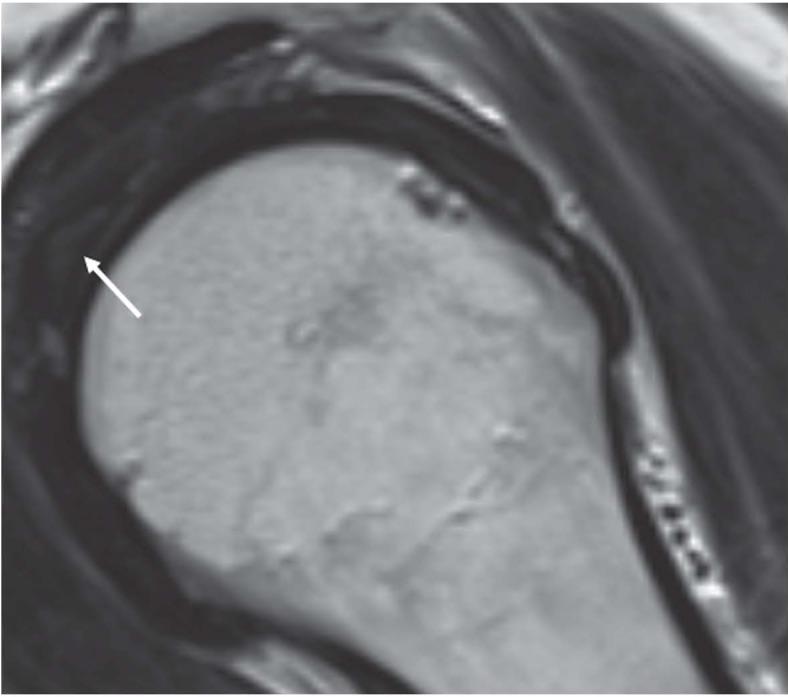

Imaging of long head biceps tendon. A multimodality pictorial essay.

The aim of this is article is to provide an  imaging review of normal anatomy, most common anatomical variants and pathologies of the long head of the biceps tendon (LHB) encountered during the daily practice.